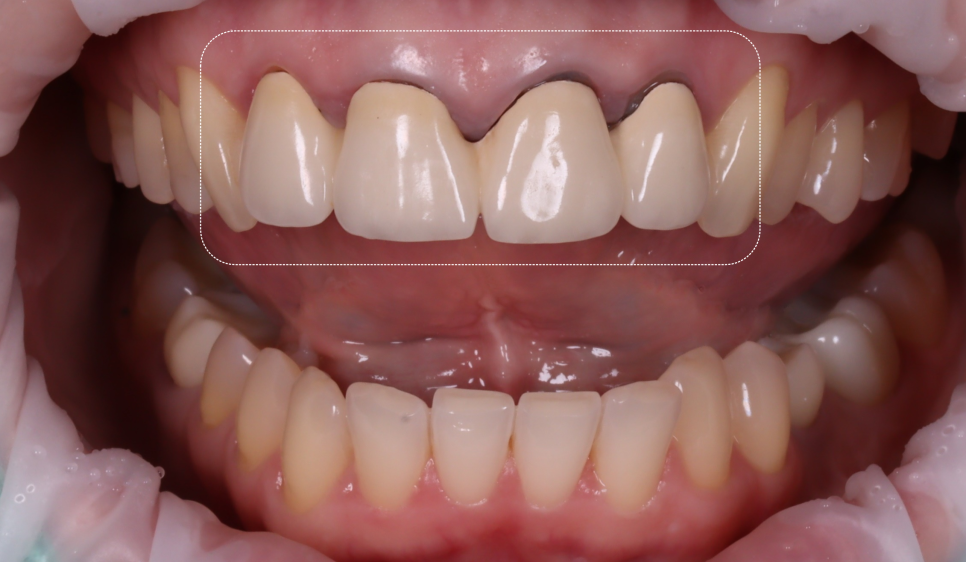

| 1) 잇몸이 검게 보임 |

촬영 : 251015

환자분의 앞니는 PFM이라는 재료로 씌워져 있었는데요.

보시는 것처럼, 가장 안에 위치한 메탈이 시간이 지나면서 잇몸이 서서히 퇴축되며 경계부가 드러나 검게 보이게 돼요.

| 3) 보철 색상이 비심미적 |

PFM이 불투명해 자연치아와의 색상이 어우러지지 않고 이질감을 주고 있었습니다.

딱 봐도 '치아를 씌운 것 같은 느낌'을 주고 있었죠.

또, 네모 박스 부분이 유독 더 노란빛이 도는데 그 점이 마음에 들지 않는다고 하셨어요.

| 4) 넙데데해 보이는 형태 |

앞니의 뒤 라인이 너무 넙데데하게 생긴 것이 마음에 들지 않는다고 하시더라고요.

제가 봤을 때, 앞니의 중앙이 볼륨이 없어 납작하고, 말씀하신 것처럼 끝의 라인이 바로 옆 치아와 이어져 넙데데하고 치아가 커 보이기까지 하더라고요.

| 5) 얼굴과 치아 축의 틀어짐 |

이렇게 선을 그어보면 틀어진 축을 볼 수 있습니다.